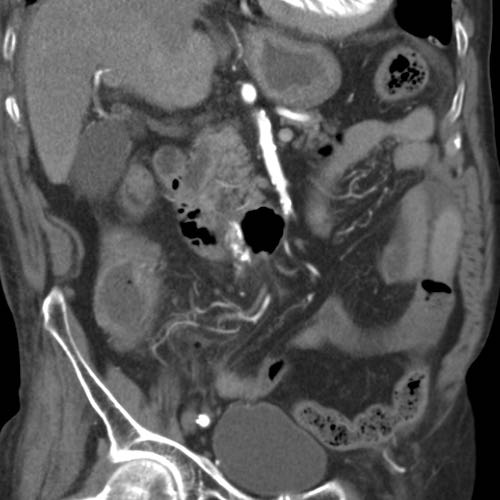

Bệnh nhân nữ 74 tuổi nhập viện với đau bụng dưới sâu kéo dài 3 tuần. Xét nghiệm: bạch cầu 15, CRP 150. Bệnh nhân có tiền sử nhiều lần phẫu thuật phụ khoa.

CT được thực hiện và phát hiện một dị vật dạng xương, với cả hai đầu đều có vẻ xuyên thủng đại tràng sigma.

Siêu âm qua đường âm đạo xác nhận dị vật đi xuyên qua lòng đại tràng sigma, do đó có thể lấy dị vật qua nội soi đại tràng.

Trong quá trình nội soi, xương gà phải được bẻ làm hai phần để lấy ra an toàn. Bệnh nhân hồi phục tốt với sự hỗ trợ của kháng sinh.